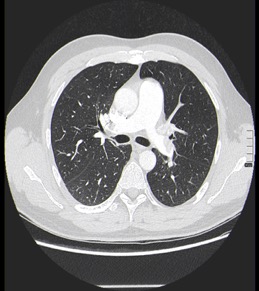

Nuestro paciente tiene síntomas respiratorios y un valor elevado de Dímero D. El Angio-TC nos permite hacer una valoración más detallada del estado de la anatomía vascular pulmonar así como del del corazón: También nos va a proporcionar una visión más en detalle del parénquima pulmonar.